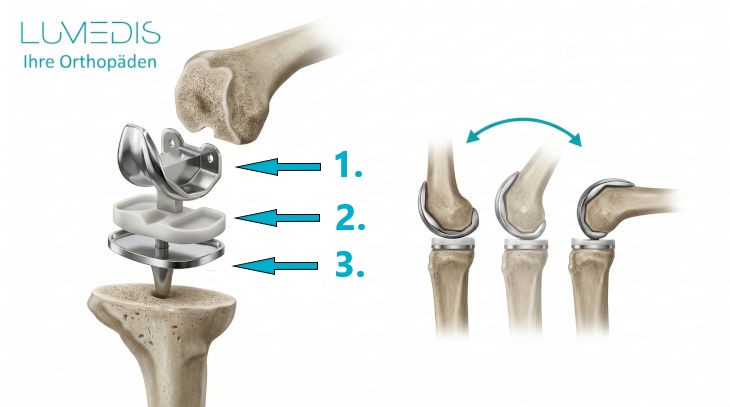

Welche Arten von Knieprothesen gibt es?

Die Knieprothesen können nach verschiedenen Gesichtspunkten eingeteilt werden.

Allgemein wird unterschieden zwischen dem Ersatz des gesamten Kniegelenks und einem Teilersatz:

- Die Knie-Totalendoprothese (KTEP) umfasst dabei den künstlichen Ersatz aller Gelenkanteile, also dem Oberschenkel- und Schienbeinknochen, sowie in einigen Fällen auch der Kniescheibenrückseite.

Weiterhin spielt die sogenannte Koppelung, also eine mechanische Bindung der Prothesenteile, eine Rolle:

- bei intaktem Bandapparat des Kniegelenks werden die Prothesenteile ungekoppelt eingebaut, das bedeutet, dass der Oberschenkel mit dem Unterschenkel nicht durch die Prothese verbunden ist.

- Mit zunehmender Bandschädigung gibt es die Möglichkeiten einer teilgekoppelten oder vollgekoppelten Prothese.

Beim Gleitlager wird zwischen einer fixierten Version, dem fixed bearing, und dem mobileren mobile bearing unterschieden:

- Ersteres besitzt eine feste Verbindung zwischen der Gleitfläche des Oberschenkels und dem Schienbeinplateau,

- zweiteres ist hier hingegen beweglicher und damit auch näher an der Funktion des Kniegelenks, macht aber gleichzeitig auch mehr Möglichkeiten für eine Fehlfunktion.